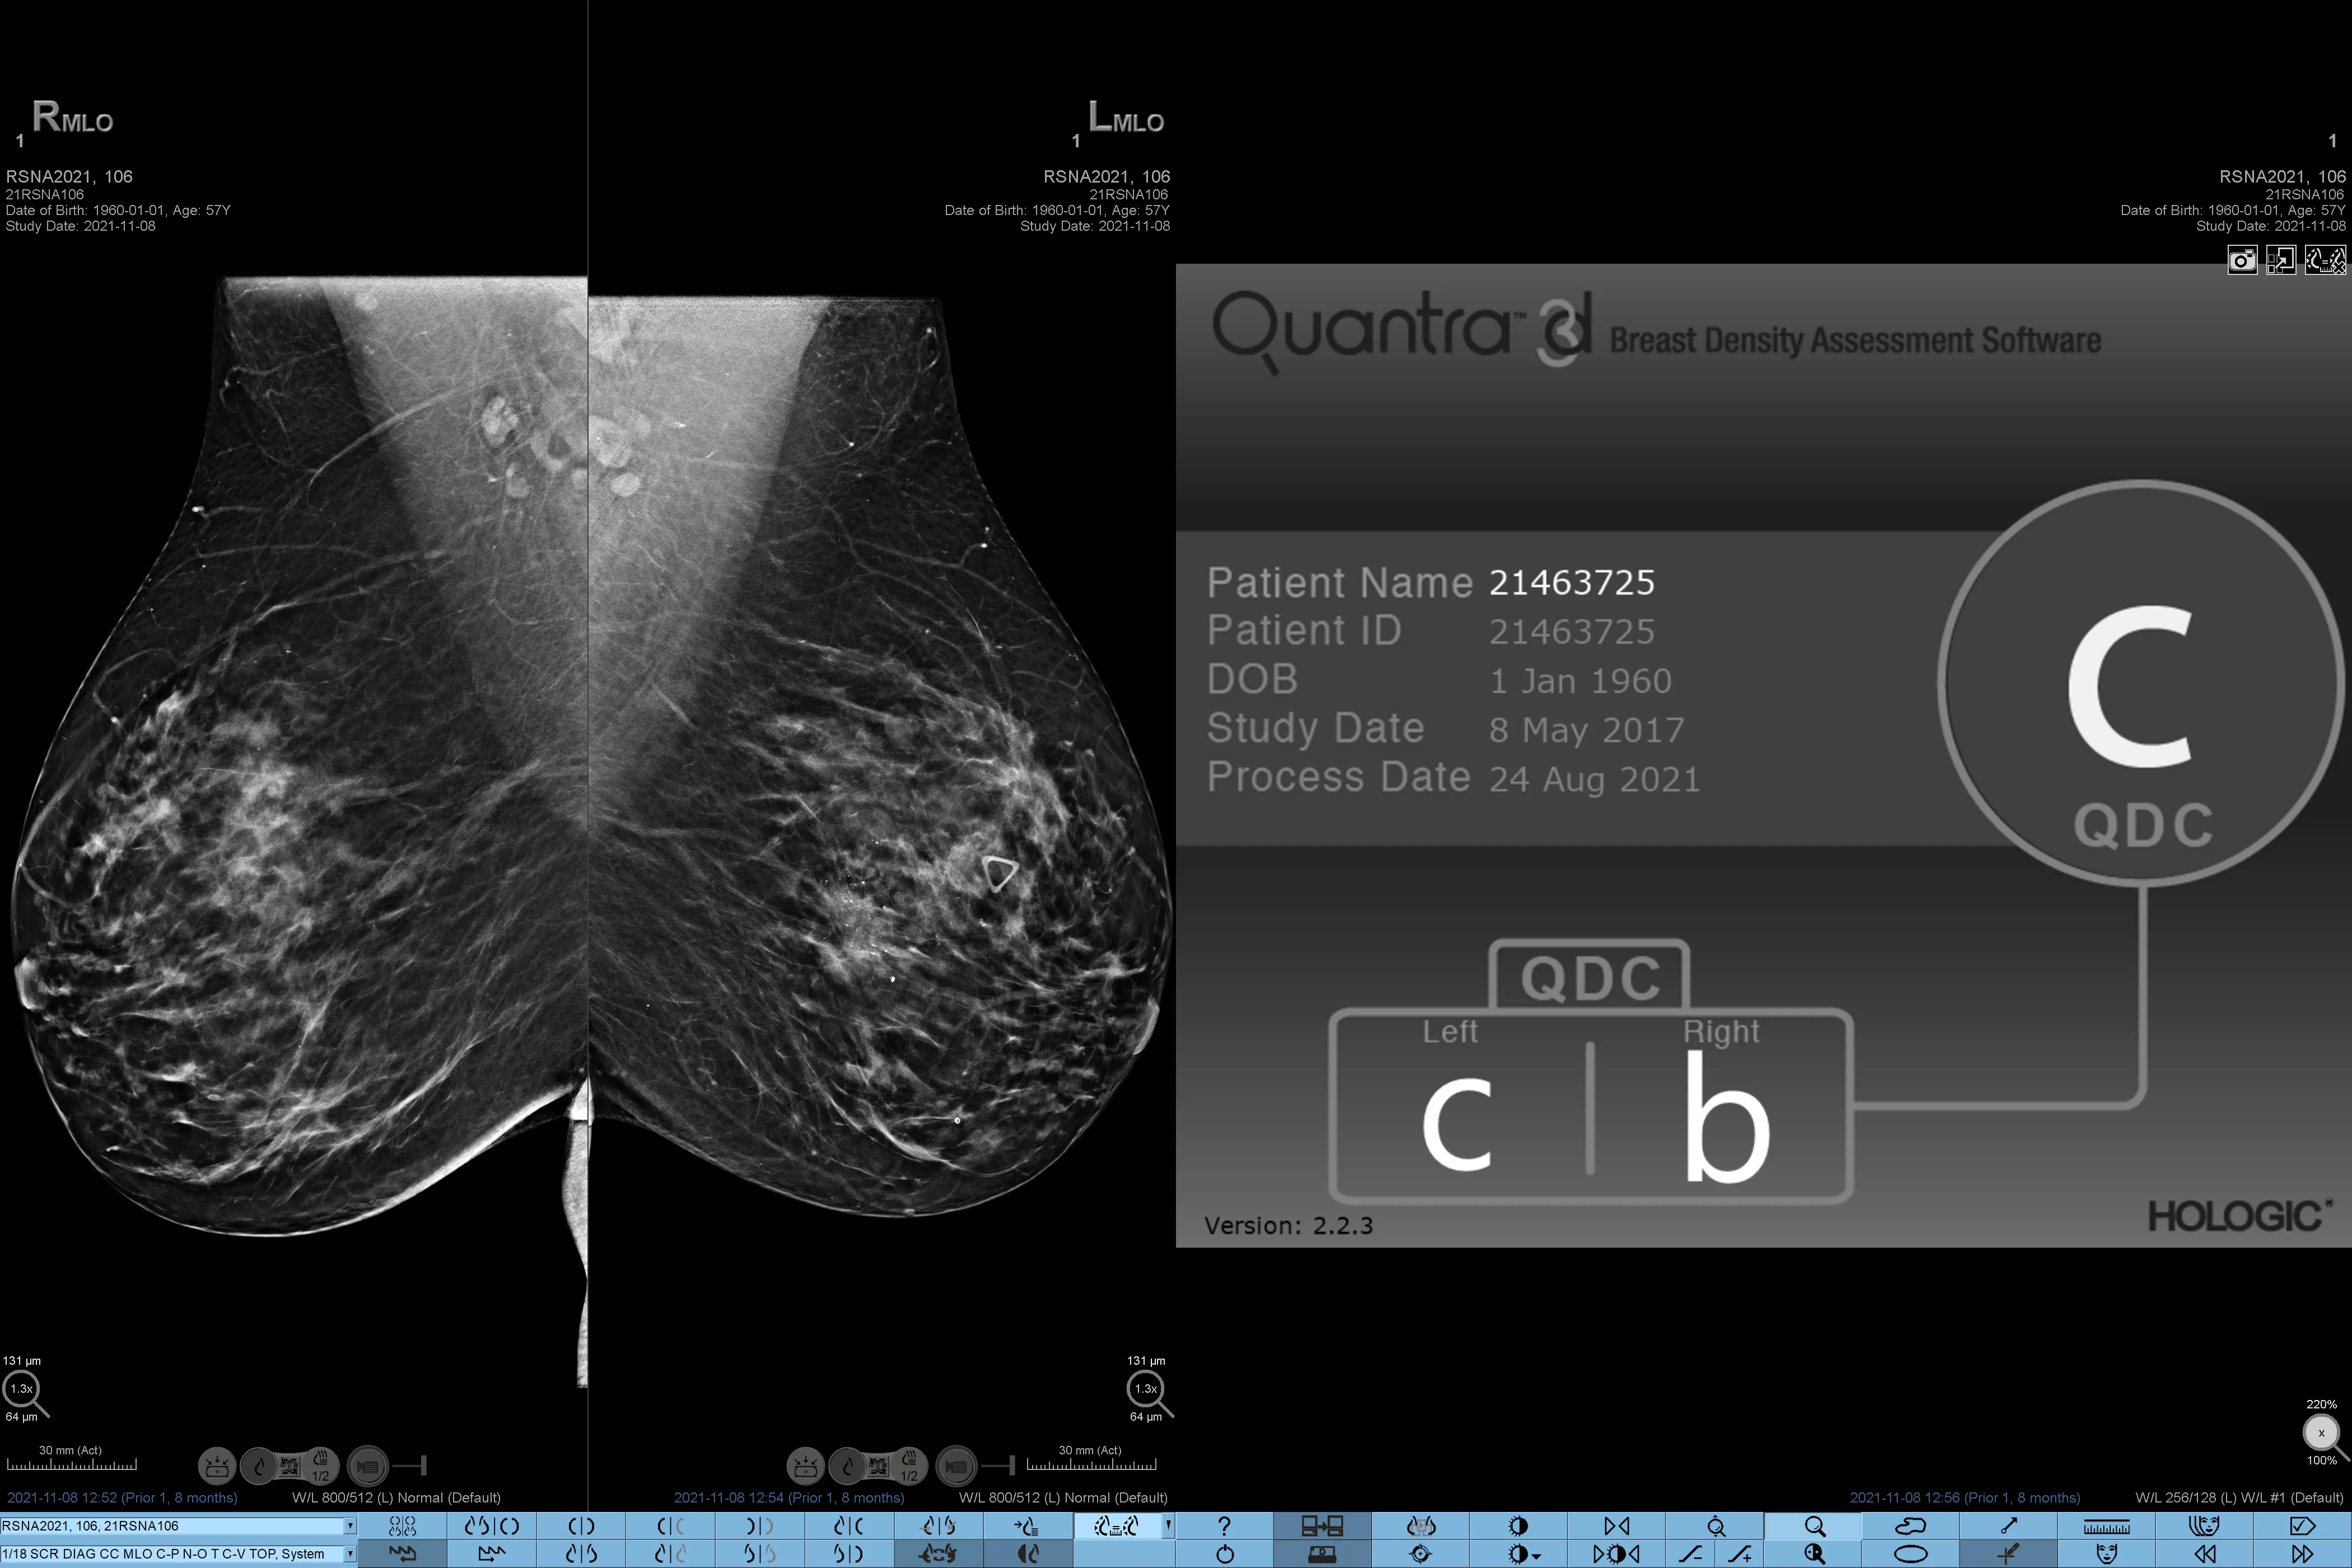

Higher breast density is known to increase a woman’s risk for breast cancer.1 The need for accurate, unbiased analysis is therefore critical. Powered by machine learning, Quantra technology software analyses both 2D™ and tomosynthesis images for distribution and texture of parenchymal tissue. It categorises breasts in four breast composition categories consistent with guidance from the American College of Radiology (ACR) BI-RADS Atlas 5th Edition.2

Objective machine learning algorithm that assigns breast density category based on analysis of breast tissue texture and patterns.

Standardisation

Standardise reporting across the radiology practice and provide a high standard of care.

Quantra software’s unbiased algorithm analyse both 2D and tomosynthesis images to support your analysis by:

• Overcoming subjectivity in visual assessment, providing more consistent, and more reliable scoring.*

*Scores are based on ACR BI-RADS categories, in line with the revised guidance by the American College of Radiation (ACR) BI-RADS Atlas 5th Edition. This accounts for pattern and texture, compared with volume, when determining density.

8. Breast composition categories as described in ACR BI-RADS Atlas.